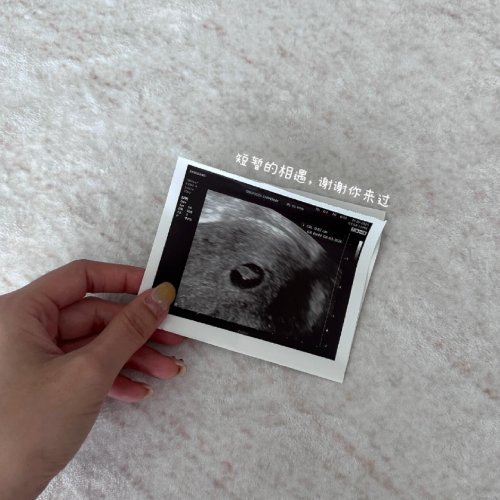

Stephy 在视频中提到,她在 6 月发现怀孕,产检显示已约 5 周。当时的她期待着能听见宝宝的心跳,但在第二次产检前出现见红等症状,便紧张就医。

7 月 17 日的第二次产检中,B 超一度无法确认宝宝是否有成长,最终经由阴超才听见宝宝的心跳声。然而两天后的早晨,她上厕所时突然发现内裤上有鲜红的血,并听见有东西排出。紧急送医后确认流产,医生也告诉她:“这不是你的错。换个角度想,宝宝或许不够健全,才会选择提早离开。”

Stephy 写道:“看着新的生命刚刚萌芽,又悄然离开,心是无比心痛……愿我们有缘再相见。” 贴文发出后,不少网友在留言区分享自身经历,表示“宝宝是为了保护妈妈,才选择自己先离开”。也有留言写道:“非常理解你的心情,感同身受。允许自己好好哭一场,休息好,养好小房子。”